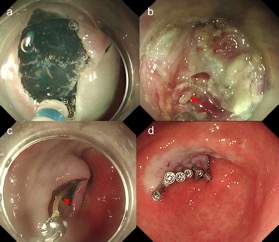

经过周密的术前准备,魏志团队为刘阿姨实施了“超声内镜定位下联合内镜下经隧道异物取出术”。术中观察在白光内镜下见十二指肠球部前壁见一黏膜下隆起,顶端充血糜烂伴有白色脓液流出,未看到明确的异物(图2)。

图2白光内镜:十二指肠球部前壁见一黏膜下隆起,

顶端充血糜烂